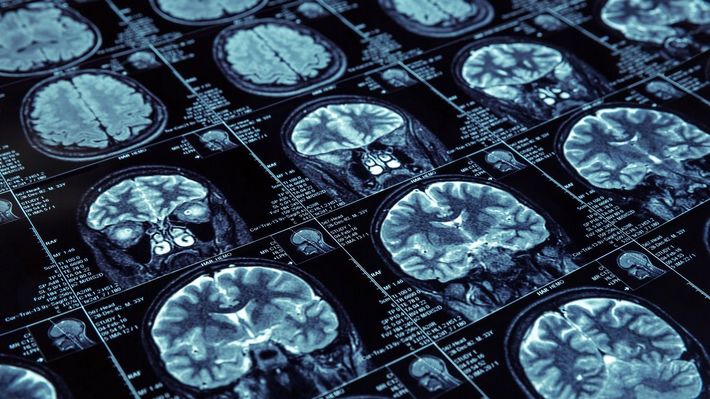

※写真はイメージです